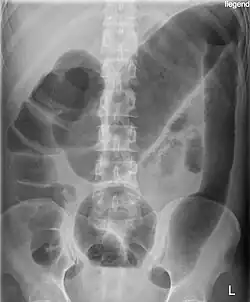

- Im akuten schwersten Verlauf kann es zur toxischen Dickdarmerweiterung kommen. Dabei findet sich eine Überblähung des Bauchraumes und eine Bauchfellentzündung, außerdem besteht die Gefahr einer Perforation, weshalb jegliche invasive Diagnostik kontraindiziert ist.